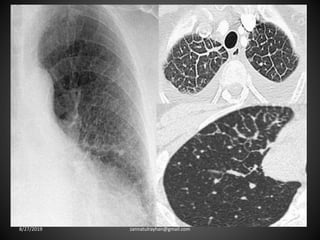

Bronchiectasis: localized bronchial dilatation.

The diagnosis is based on a combination of the

following findings:

-bronchial dilatation (signet-ring sign)

-bronchial wall thickening

-lack of normal tapering with visibility of airways in

the peripheral lung

-mucus retention in the bronchial lumen

-associated atelectasis and sometimes air trapping

8/27/2019 zannatulrayhan@gmail.com